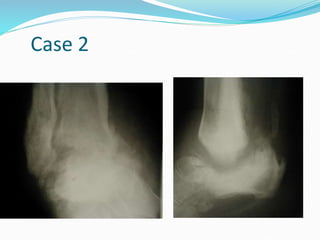

Case 2